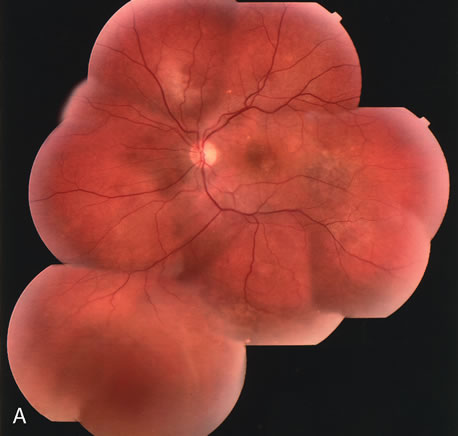

Clinically discernible peripheral dependent bullous neurosensory detachments have been described in patients with chronic CSC.85–92 Yannuzzi and co-workers first characterized the presence of RPE atrophic tracts extending inferiorly in the fundus periphery secondary to antecedent retinal detachment in patients with CSC.85 Presumably, there is a particularly severe and/or longstanding leakage of fluid from an RPE defect in the subretinal space at the posterior pole. The subretinal fluid gravitates inferiorly to form a dependent neurosensory detachment in a “flask,” “teardrop,” “dumbbell,” or “hourglass” pattern (Fig. 31). Sometimes the tract of subretinal fluid connecting the macular detachment with the bullous neurosensory detachment in the inferior hemisphere is so shallow that it is very difficult to appreciate. The RPE under the chronic retinal detachment experiences atrophic changes that appear as atrophic RPE tracts connecting the posterior pole with the dependent retinal detachment. The retina itself develops secondary manifestations including pigment migration, capillary dilatation (telangiectasia) proximally and capillary nonperfusion (ischemia) distally to the area of detached retina (see Fig. 31). The changes in the RPE consist of both RPE atrophy and pigment clumping in the form of perivascular deposits or bone spicules, a condition described by Gass as a “pseudoretinitis pigmentosa–like atypical CSC presentation.”87

Fig. 31. A 47-year-old woman with an18-year history of central serous chorioretinopathy in both eyes. A. Color photograph composite of the left eye shows bullous dependant detachment of the neurosensory retina inferiorly. B. Fluorescein angiogram composite reveals diffuse decompensation of the retinal pigment epithelium, multiple scattered pigment epithelium detachments 9PEDs), and obliteration of the retinal capillaries in the region of the detachments. Note the presence of early neovascularization at the junction between perfused and non-perfused retina. C. Clinical photograph of the left eye shows PED superior to the optic disc partially surrounded by fibrin deposits. D. Fluorescein angiography confirms the presence of active leakage from the serous PED. E, Color photograph composite of the same eye 2 months after laser treatment of the site of leakage reveals partial resolution of the detachment and lipid precipitation. F. Clinical photograph composite 16 months after the laser treatment in the area of the leakage shows complete resolution of the detachment and partial reperfusion of the inferior retina.